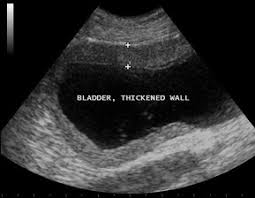

What Are Symptoms Of Bladder Cancer In Cats - Bladder Cancer Treatment Pdq Patient Version National Cancer Institute / Other signs that your cat could have a cancer of the bladder would be when you notice that the animal spends a lot of time trying to urinate but a very small volume of urine actually does come out.. Bladder stones are relatively common in cats and cause signs similar to those seen with bladder cancer. Bladder stones irritate the lining of the bladder blood in the urine, straining to urinate and increased frequency of urination. A lot of cat cancer symptoms can be illness or other diseases too. Unusual lumps or swellings anywhere on your cat's body, especially if they're getting larger or changing shape.; Tumors of the ureters, bladder, and urethra can cause hematuria (blood in the urine), dysuria (straining to urinate), difficulty urinating, and frequent urination.

The lymph nodes behind the knees and under the jaws are easiest to find. Rhabdomyosarcoma of the urinary bladder may be reported as botryoid rhabdomyosarcomas due to their tendency to take on the appearance of grape clusters. Cat bladder cancer is usually suspected in older cats that end up having recurring urinary tract infections. Other signs that your cat could have a cancer of the bladder would be when you notice that the animal spends a lot of time trying to urinate but a very small volume of urine actually does come out. If your cat is eating less but seems to be bulking up, take a trip to the vet, says rocha. The signs of urinary tract tumors depend on what area of the urinary system is affected. Other signs of cancer in cats : The cause is often stress, which causes inflammation of the nerves in the bladder wall. Chris vanderhoof, dvm, mph 3 comments on bladder stones in cats: The veterinarian will perform a complete physical examination of your cat, which will include a rectal exam. Bladder stones irritate the lining of the bladder blood in the urine, straining to urinate and increased frequency of urination. Bladder symptoms are more likely to come from conditions other than cancer. Untreated bladder stones can lead to a number of problems.

If your cat's uretha becomes blocked and he can't urinate, he could die from a condition called uremia, in fewer than three days. This form of cancer affects the bladder and may even block the urinary tract completely. Swollen lymph nodes are a symptom of lymphoma. Chris vanderhoof, dvm, mph 3 comments on bladder stones in cats: Bladder cancer symptoms cat bladder cancer symptoms include difficulty urinating, frequent need to urinate while passing only small amounts of urine, blood in the urine, straining to defecate, and difficultly breathing. These symptoms overlap with those common in urinary tract infection, therefore, these symptoms alone do not necessarily mean that the pet has tcc. Clinically, it should be noted that the onset of signs for cat bladder infection are acute (suddenly noticeable) and sudden. Cat bladder cancer is usually suspected in older cats that end up having recurring urinary tract infections. Other signs of cancer in cats : The most common urinary bladder cancer symptoms include: Causes, symptoms & treatment by dr. Unusual lumps or swellings anywhere on your cat's body, especially if they're getting larger or changing shape.; Bladder stones irritate the lining of the bladder blood in the urine, straining to urinate and increased frequency of urination.